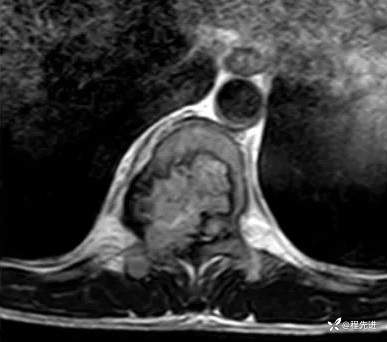

患者性别:男

患者年龄:29岁

简要病史:双下肢麻木无力5月余,有踩棉感

T2横断位: